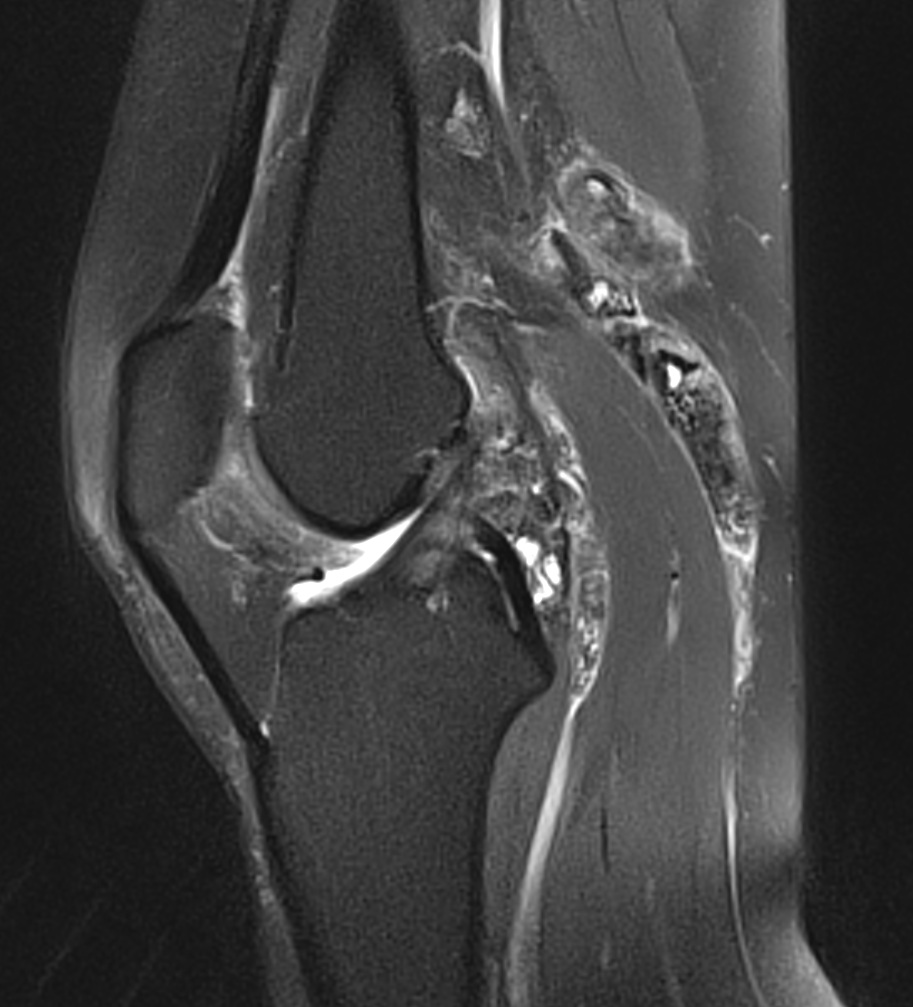

Synovite villo-nodulaire du genou